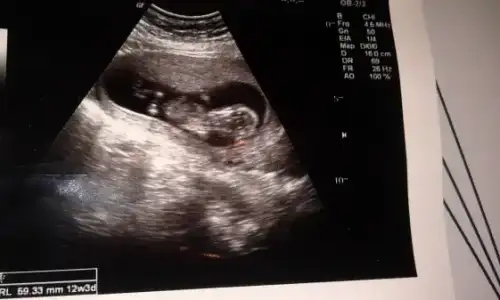

dr soylemeden siz gorun genital nub teorisi ( bebegin cinsiyeti)

pek tecrubeli degilim..yani cok onemsemeyin ama bence erkek ;)

nub buyuk geldi banaaa..kizlar duzeltsinler ama bence erkek

ya benim bebeğim cinsiyeti tahmin eden var mi? erkeğe benziyor dedi ama kesin degil dedi bi doktor da kız gibi kafam karisti

Arkadaşlar ablamında benimde bebeğin cinsiyeti sanırım netleşti.

bizim dr kesin erkek dedi ablamın dr da erkek gibi kıza pek heveslenme demiş=(